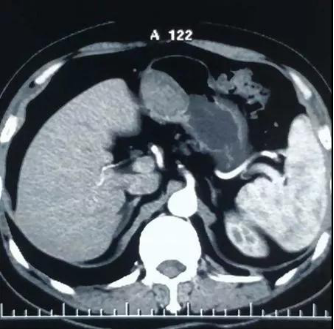

近日,市中医院消化内科在胃镜下通过微创技术,为利州区宝轮镇新街4组余××成功挖出了直径达5公分如土豆大小的“胃间质瘤”,术后恢复良好,痊愈出院。

胃间质瘤是医学上的新词,是21世纪才正式命名和普遍使用的医学新名词。这种病变在胃镜下的形态学表现和我们常说的胃癌、胃淋巴瘤、胃息肉能直接区分开,因为它生长源于固有肌层,像土豆生长一样,可以通过超声内镜检查和CT检查确诊。